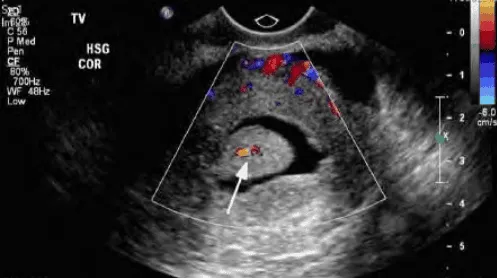

Siêu âm bơm nước: Với u xơ dưới niêm mạc.

Hình ảnh “U xơ tử cung FIGO 0 trên SIS”.

Hình ảnh “Phân biệt polyp và u xơ tử cung FIGO 1 bằng Doppler”.